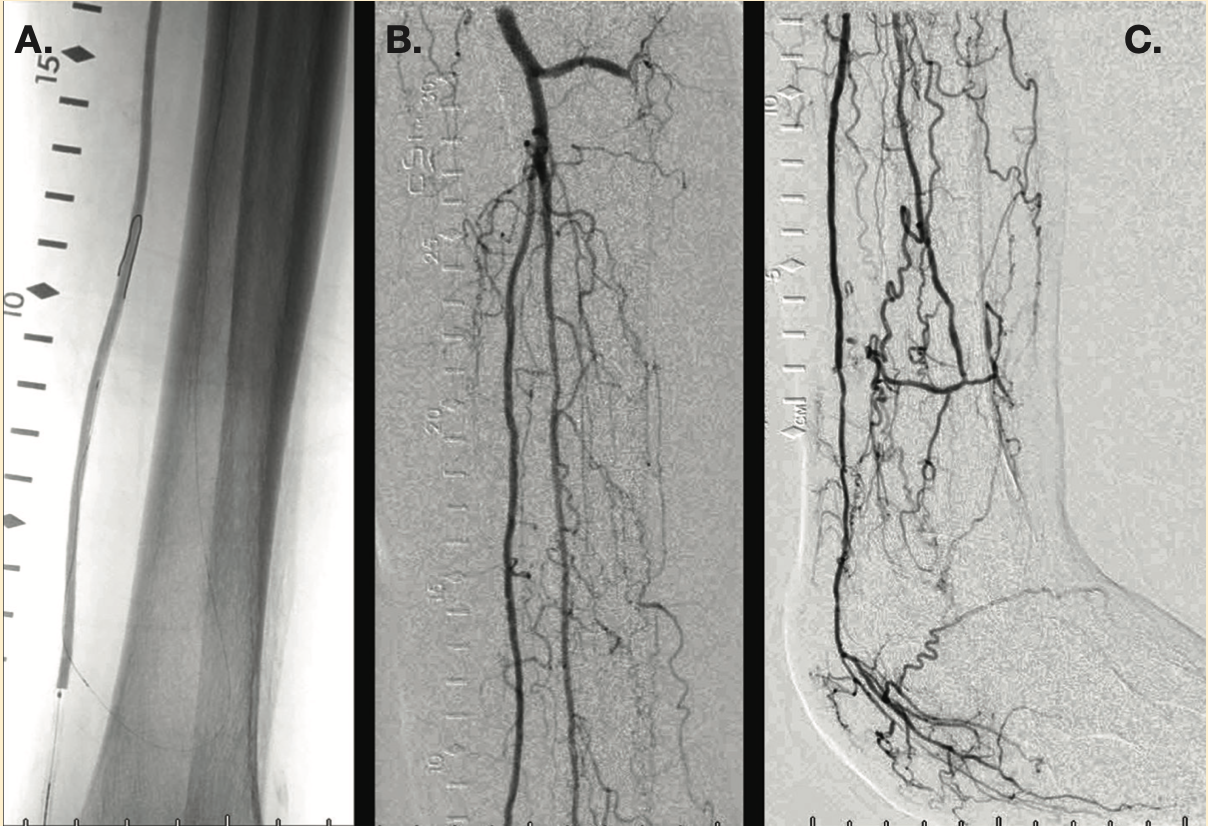

This is an 81-year-old female with a 5-week history of left heel ulceration. Her past medical history includes diabetes mellitus, hypertension, chronic kidney disease stage IV, and dyslipidemia. She is status post right above-knee amputation. Physical exam revealed palpable femoral pulses and no distal pulses in the left foot. Left ankle-brachial index (posterior tibial artery) was 0.36.